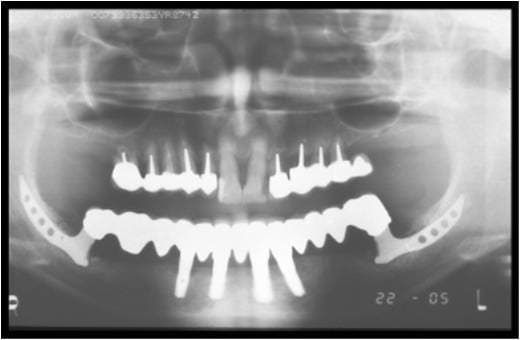

En stock, j'ai cela aussi. C'est quoi.

Image1 hcff4v - Eugenol

Image2 ok8ysy - Eugenol

Ce sont des implants ramiques...

Très très difficiles à poser mais qd ça marche c est bien

Difficultés

1. aucun outil normé pour tailler la tranchée

2. nécessité d avoir de la hauteur encore au dessus du NDI